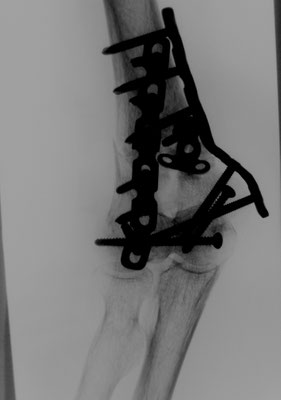

Ellenbogennaher Oberarmbruch/suprakondyläre Oberarmfraktur

Diese Brüche gehen häufig mit einer erheblichen Zertrümmerung des Knochens einher. In den meisten Fällen ist auch die Gelenkfläche betroffen, so dass eine operative Rekonstruktion erforderlich ist. Wie bei allen gelenknahen Knochenbrüchen besteht die Aufgabe darin, ein sehr kurzes Knochenfragment an dem Schaftknochen zu befestigen und die Gelenkfläche stufenlos wieder herzustellen. In der Standardtechnik werden dabei zwei Platten benutzt. Dabei geben insbesondere die winkelstabilen Titanplatten optimale Möglichkeiten um die kleinen Knochenteile stabil zu befestigen.

Ist allerdings die Gelenkfläche so stark zerstört, dass eine Rekonstruktion nicht möglich ist, bietet sich bei Patienten in höherem Lebensalter die Implantation einer Ellenbogenprothese an. Mit dieser ist eine gute Funktion zu erreichen.